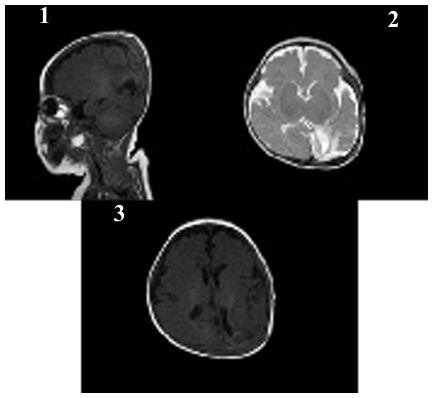

After 11 days of treatment, physical examination revealed mild swelling and redness in the posterior fontanelle area at the midline and slightly to the left of the occipitoparietal region, ap proximately 3 cm in diameter, soft in texture with slight fluctua t ion. The brain enhanced MRI showed abnormal enhancement signals in the right parietal lobe and the left parieto-occipital area, suggesting an infectious lesion. Brain tissue was under compression and midline shift were observed (Figure 1). After the child was diagnosed with brain abscess, he was transferred to the neurosurgery department for further treatment. The sur gery of brain abscess drainage and external subdural effusion drainage was performed under general anesthesia with tracheal intubation. During the operation, a cyst infection was observed, and it eroded the underlying dura mater, with tight adhesion between the cyst wall, brain tissue, and dura mater surrounding the dura mater, thickening of the dura mater, and necrosis of the surrounding brain tissue. The infected cyst wall was separated from the surrounding dura mater, carefully dissected from the lateral to the midline to the brain tissue interface, with protec t ion of the sagittal sinus at the midline, and deep erosion of the falx cerebri. The infected cyst had broken through to the oppo site side. The right dura mater was incised, and the infected cyst and necrotic brain tissue were thoroughly removed, connecting both sides. The defected skull was about 1x3 cm in size (Figure 2). Infected DSTs and ruptured DCs with parieto-occipital brain abscess were resected (Figure 3). Postoperative pathological examination showed that purulent inflammation with abscess formation was formed. After surgery, the child was treated with meropenem (0.2 g Q8H 21d) and linezolid (0.05 g Q8H 21d) to resist infection. The child recovered smoothly after surgery, and follow-up showed good growth, with no recurrence or neuro logical sequelae (Figures 4 & 5).

Figure 5: Three-month postoperative follow-up examination. (1) Softening foci in the right parietal and left parieto-occipital lobes were more localized. (2) Bilateral parietal short T1 signals had essentially resolved. (3) Bilateral frontotemporal epidural space remained slightly widened; previously noted subdural effusion was no longer visible.